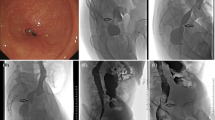

Chest CT and esophagogram or endoscopy was conducted, and all patients were as asked to fast for at least 8 h before the dilatation procedure (Fig. 1). Dilatation procedures were performed under either endoscopic or fluoroscopic guidance. The operators are endoscopists or interventional doctors with at least 10 years of work experience to avoid complications due to their operational inexperience. About 10 ml of iodine contrast was taken orally to show the stricture. A 5 F multipurpose catheter (Cook Corporation, Bloomington, USA) and guidewire were passed through the stricture. Small balloon (< 25 mm in diameter, Bard Peripheral Vascular, Inc; Cook Corporation, Bloomington, USA), large balloon (25–30 mm in diameter, Bard Peripheral Vascular, Inc; Cook Corporation, Bloomington, USA) or DCB (12 mm in diameter, 40, 60–120 mm in length, Beijing Xianreida Medical Technology Co., LTD) was delivered and dilated for 1–3 min (Fig. 2). An immediate esophogram was conducted to show the relief of stricture and the potential complication of rupture.

A male patient with caustic esophageal stricture underwent DCB dilatation. (a) Esophagogram showed esophageal stricture at the level of the middle esophagus. (b) Endoscopic view of severe stricture through which the endoscope could not be passed. (c) A guidewire was passed through the stricture, and the first session of DCB (12 mm in diameter, 40 mm in length) dilatation was done after positioning the balloon within the stricture. (d) A postdilation was performed with an 18 mm small balloon (Bard Peripheral Vascular, Inc) for the patient due to residual stenosis after DCB dilatation. (e) Two day after dilatation, esophagography showed a relief of esophageal stricture, without esophageal rupture. (f) Recurrent stricture was observed 2.1 months after dilatation. (g) For the second session of DCB dilatation, a DCB catheter with 12 mm in diameter and 40 mm in length was used for dilatation. (h) Subsequently, a postdilation was immediately performed with a 20*55 mm small balloon (Cook Corporation, Bloomington, USA). (i) Repeated reintervention of DCB (12 mm in diameter, 40 mm in length) dilatation and insertion of 18*100 mm Bona stent is performed due to recurrent stricture 3.4 months after first dilatation.